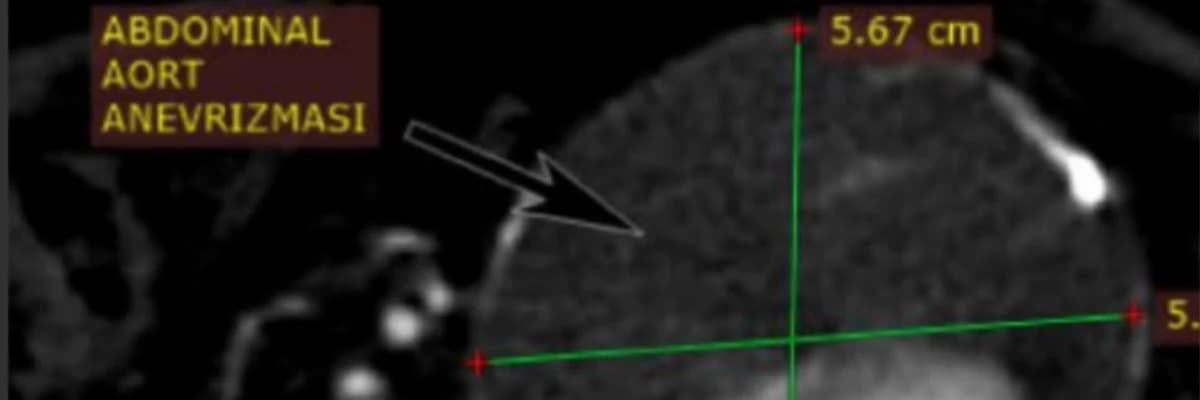

- Abdominal Aort Anevrizması (AAA): Karın bölgesinde gelişen genişlemelerdir.

| BT Anjiyografi | Anevrizma çapı ve yayılımını en ayrıntılı gösteren, cerrahi planlamada kullanılan temel yöntemdir. |